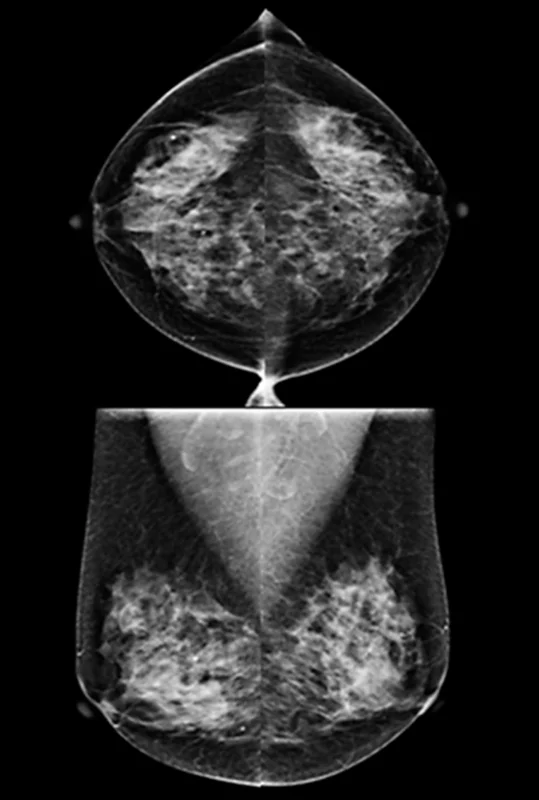

6. Glándula Mamaria

Tejido exocrino especializado; el enfoque de los estudios de imagen se centra en el diagnóstico oncológico precoz. La mamografía ha demostrado ser el pincipal estudio de imagen de despistaje de lesiones malignas.

Mastografía (10/10): Técnica fundamental para el tamizaje, capaz de identificar microcalcificaciones pleomórficas sospechosas.

Ecografía (8/10): Complemento esencial en mamas densas o para la diferenciación entre lesiones quísticas y sólidas.

Resonancia Magnética (7/10): Indicada en la evaluación de implantes o en discrepancias diagnósticas complejas.

Nota: El diagnóstico de certeza es exclusivamente histopatológico mediante biopsia dirigida.